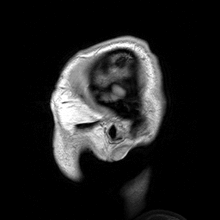

Bu alanda çalışan medikal fizikçiler klinikler bulunan görüntüleme cihazlarıyla ilgilenirler. Ayrıca araştırma kısmında çalışanlar bu cihazların geliştirir ve yeni teknolojiyi bu cihazlara uygularlar. Radyolojik görüntüleme, momografi, bilgisayarlı tomografi ve MRI cihazlarının kullanımı ve görünütü alımının doğruluğu test ederler. Bütün bunlara ek olarak görüntülemede çalışan medikal fizikçiler nükleer tıp ve uygulamaları, tek fotonlu bilgisayarlı tomografi ve pozitron tomografisi hakkında geniş bilgiye sahiptirler.Görüntülemede çalışan medikal fizikçiler knilikle içiçedirler ama bazen eğitim amaçında bilgileri paylaşırlar ve yeni metodların gelişiminde üniversiterle beraber çalışmaktadırlar.